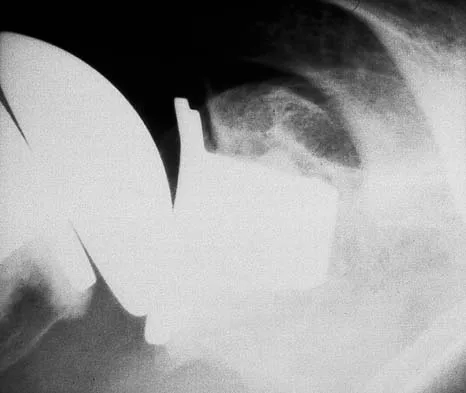

Figure 14 shows the AP radiograph of a patient who underwent prosthetic arthroplasty 8 years ago and has now become symptomatic again over the past 18 months. A WBC count and erythrocyte sedimentation rate are within normal limits, and aspiration of the glenohumeral joint yields a negative Gram stain and cultures. Which of the following procedures will most likely provide the best pain relief and function?

Explanation